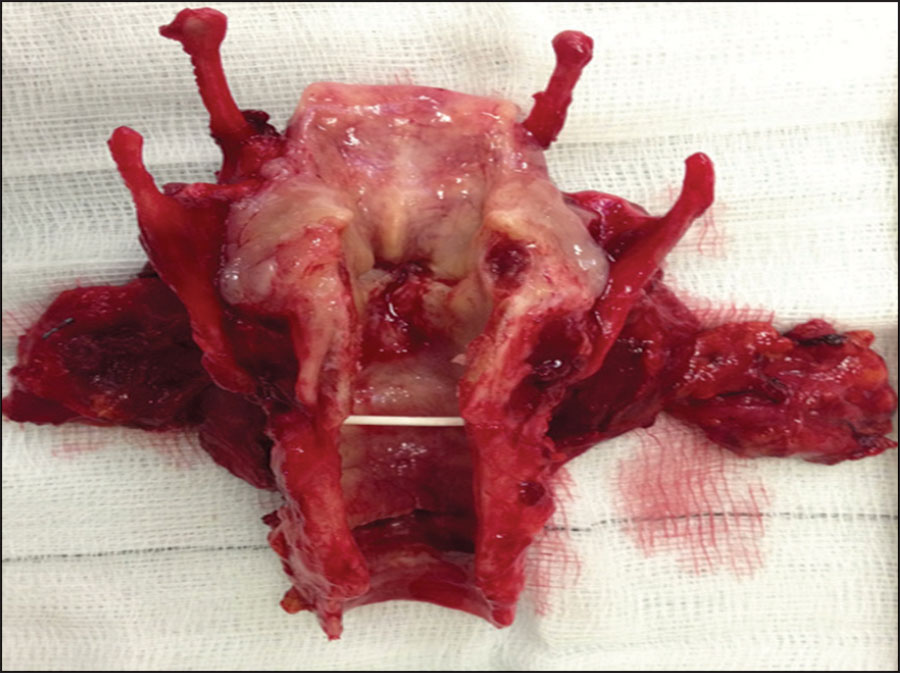

Figure 1. Total laryngectomy for a transglottic T4 SCC cancer

Figure 1. Total laryngectomy for a transglottic T4 SCC cancer(click to enlarge)